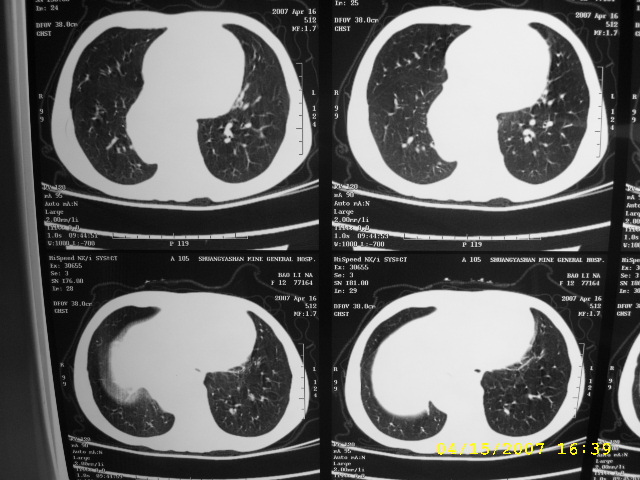

女,12,后纵隔占位十余年。

女,12,后纵隔占位十余年,没什么特异性,考虑1纵隔囊肿2肺隔离症3神经源性肿瘤,建议增强

考虑:1 支气管囊肿. 2 神经源性肿瘤;建议增强扫描。

支气管囊肿或食管囊肿可能性大,建议mri检查。